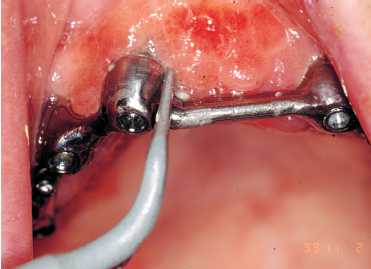

Figuras 2a y 2b. Adiestramiento en la clínica con el

paciente de la utilización de superflos y cepillos interproximales